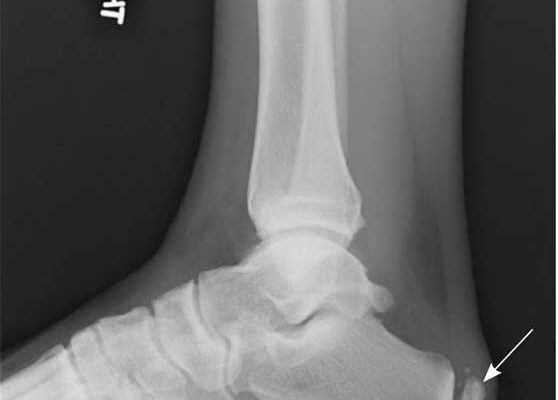

• Стресові переломи.

• Спур (новоутворення) п’яткової кістки.